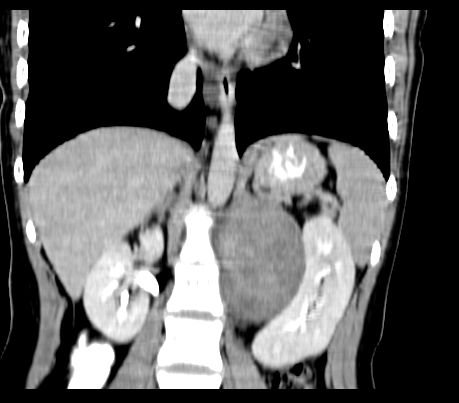

腹部平扫

动脉期